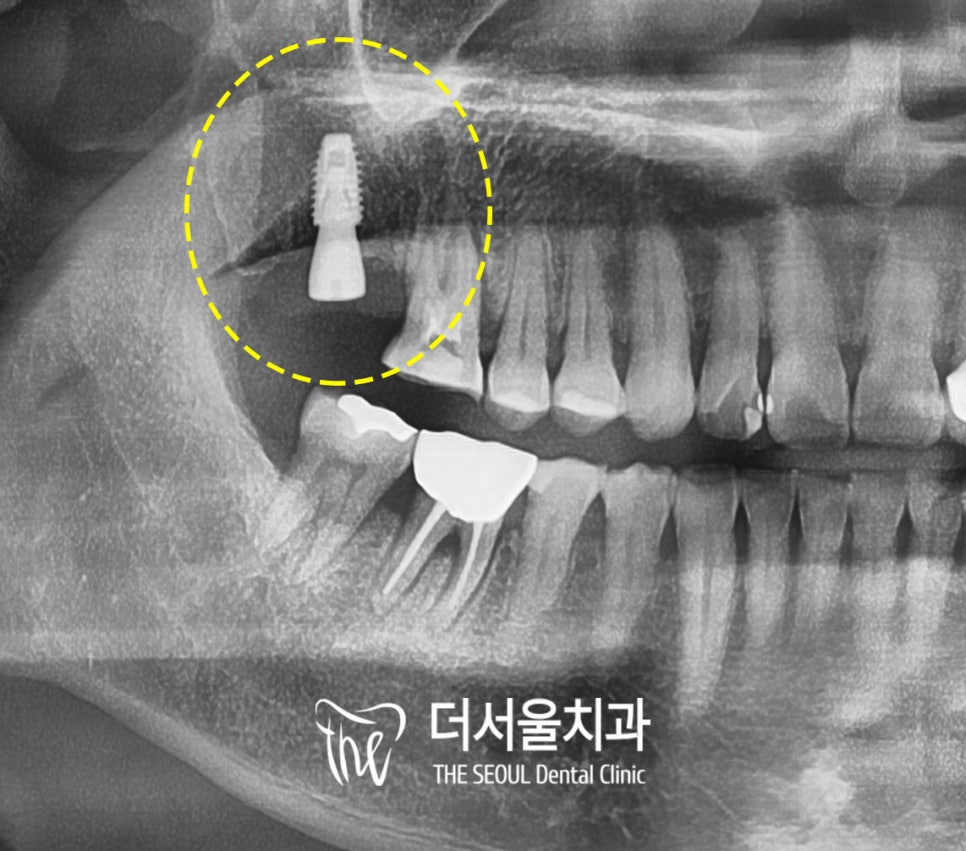

3차원 방사선 CT로

픽스처가 식립될 위치와 방향을

미리 예측합니다.

이때는 상악동이라는 코뼈 옆의

비어있는 빈 공간을

건들지 않게 조심해야 되기에

더서울에서는 3D 입체 시스템을 이용해서

픽스처의 두께와 길이를 조절하고

이에 맞는 적절한 위치에

인공치근을 심는답니다.

또한 구강 중 맨 뒤쪽 자리에 식립해야 되니

기구의 접근이 어려울 수 있어

이때는 전문의의 숙련된 노하우와

풍부한 경험이 중요합니다.

환자도 열심히 입을 크게 벌려주시면 더 좋고요^^

그 앞에 금이 간 #16도

통증을 느끼는 치수를 제거하는

신경치료를 해줄 예정입니다.